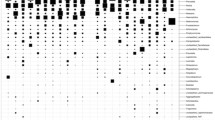

DESeq2 analysis revealed several taxa belonging to genera Solobacteria, Peptostreptococcus, Catonella, Finegoldia, Campylobacter, Prevotella, and Capnocytophaga with significantly higher abundances in the cancer tissues when compared to the tissues of control subjects (P < 0.01).The genera Corynebacterium, Actinomyces, Rothia and Streptococcus were significantly greater in the controls (P < 0.01) (Fig. 2). Nineteen metabolic pathways were found to be differentially abundant between cancer tissue bacteriome and normal tissue bacteriome (Fig. 3). The MA-plots for the DESeq2 analysis is provided in the supplementary material.

Oral cancer bacteriome differs between matched tumor surface and deep tumor tissue samples

The bacterial community of matched tumor surface mucosa and tumor tissue differed significantly, both at the community level (Fig. 4A) as well as at taxonomic levels (Fig. 4B,C). The PCA plot for the groups is illustrated in Fig. 4D. There was a significant difference in the abundance of phyla Bacteroidetes and Fusobacteria on tumor surfaces illustrating a lesser proportion of the former and higher proportion of the latter in comparison to matched cancer tissues. Especially, the abundances of taxa belonging to genera Porphyromonas, Enterobacteriae, Neisseria, Streptococcus and Fusobacterium were significantly elevated on the tumor surfaces: Prevotella, Treponema, Sphingomonas, Meiothermus and Mycoplasma genera were significantly more abundant in matched deep tumor tissue samples (Fig. 5). Twenty-four metabolic pathways were found to differ between tumor surface and deeper tissue (Fig. 6). The most abundant pathways were those related to fatty-acid biosynthesis, carbon metabolism and amino-acid metabolism on the tumor surface: carbohydrate metabolism and organic polymer degradation were elevated in cancer tissues.